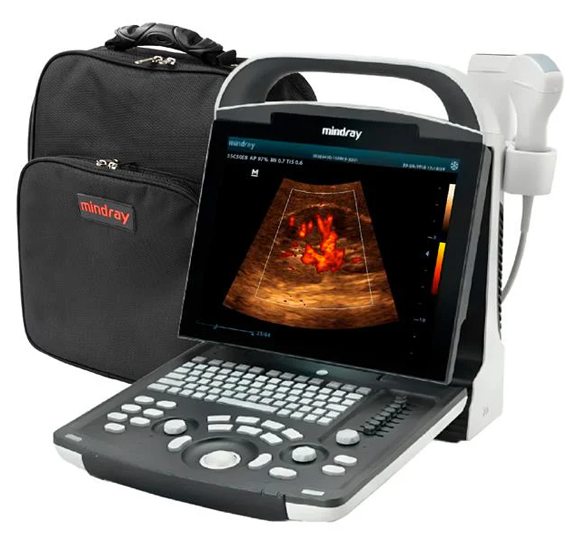

DP-20

Sistema de ultrasonido.

La opción ideal para un sistema de ultrasonido blanco y negro básico, ofrece una combinación excepcional de rendimiento y precio asequible. Con una nueva plataforma basada en el potente procesador Intel, el DP-20 forma parte integral de la nueva generación de sistemas de ultrasonido blanco y negro portátiles de Mindray, equipados con las últimas tecnologías de imagen y prácticas opciones de flujo de trabajo.